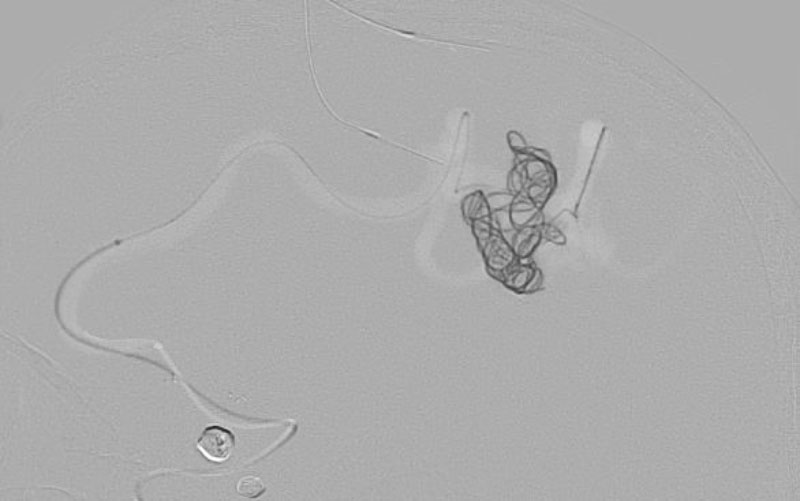

No.1585 手術中